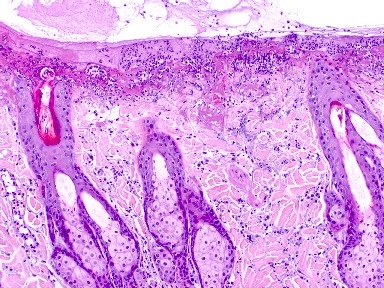

Fig. 3 Biopsia. Infiltrado inflamatorio de perivascular a intersticial de mastocitos, eosinófilos y neutrófilos